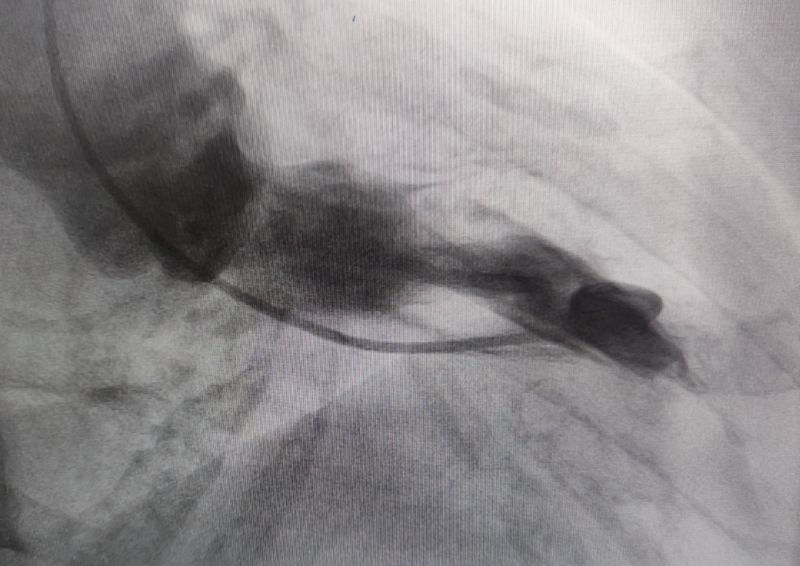

消融后造影

測壓

消融時測壓

經過多輪嚴謹的術前討論,在吳棟梁院長的專業指導下,崔旭輝主任醫師團隊決定在臨時起搏器的安全保護下,為患者實施冠狀動脈造影術及室間隔化學消融術。術中,團隊通過造影精準鎖定第一穿隔支為消融靶血管。測壓數據顯示:左室壓260/15mmHg,流出道173/6mmHg,主動脈壓106/70 mmHg,壓力階差達87mmHg。隨后,團隊使用2.0X15mm預擴球囊以8atm壓力阻斷第一穿隔支遠端血流1分鐘,再次測壓時,壓力從269/7mmHg驟降至174/4mmHg,這一結果充分證實該血管正是室間隔的有效供血血管。緊接著,團隊通過SPRINTER OTW2.0×8mm球囊緩慢注入1.4ml無水酒精。10分鐘后復測,左心室壓降至136/5 mmHg,主動脈壓為112/93 mmHg。術后第2天,王女士胸悶、氣短、心悸等不適癥狀完全消失。復查心臟彩超顯示:EF值與FS值保持穩定,收縮期左室流出道血流速度降至252cm/s,PG值為25mmHg。